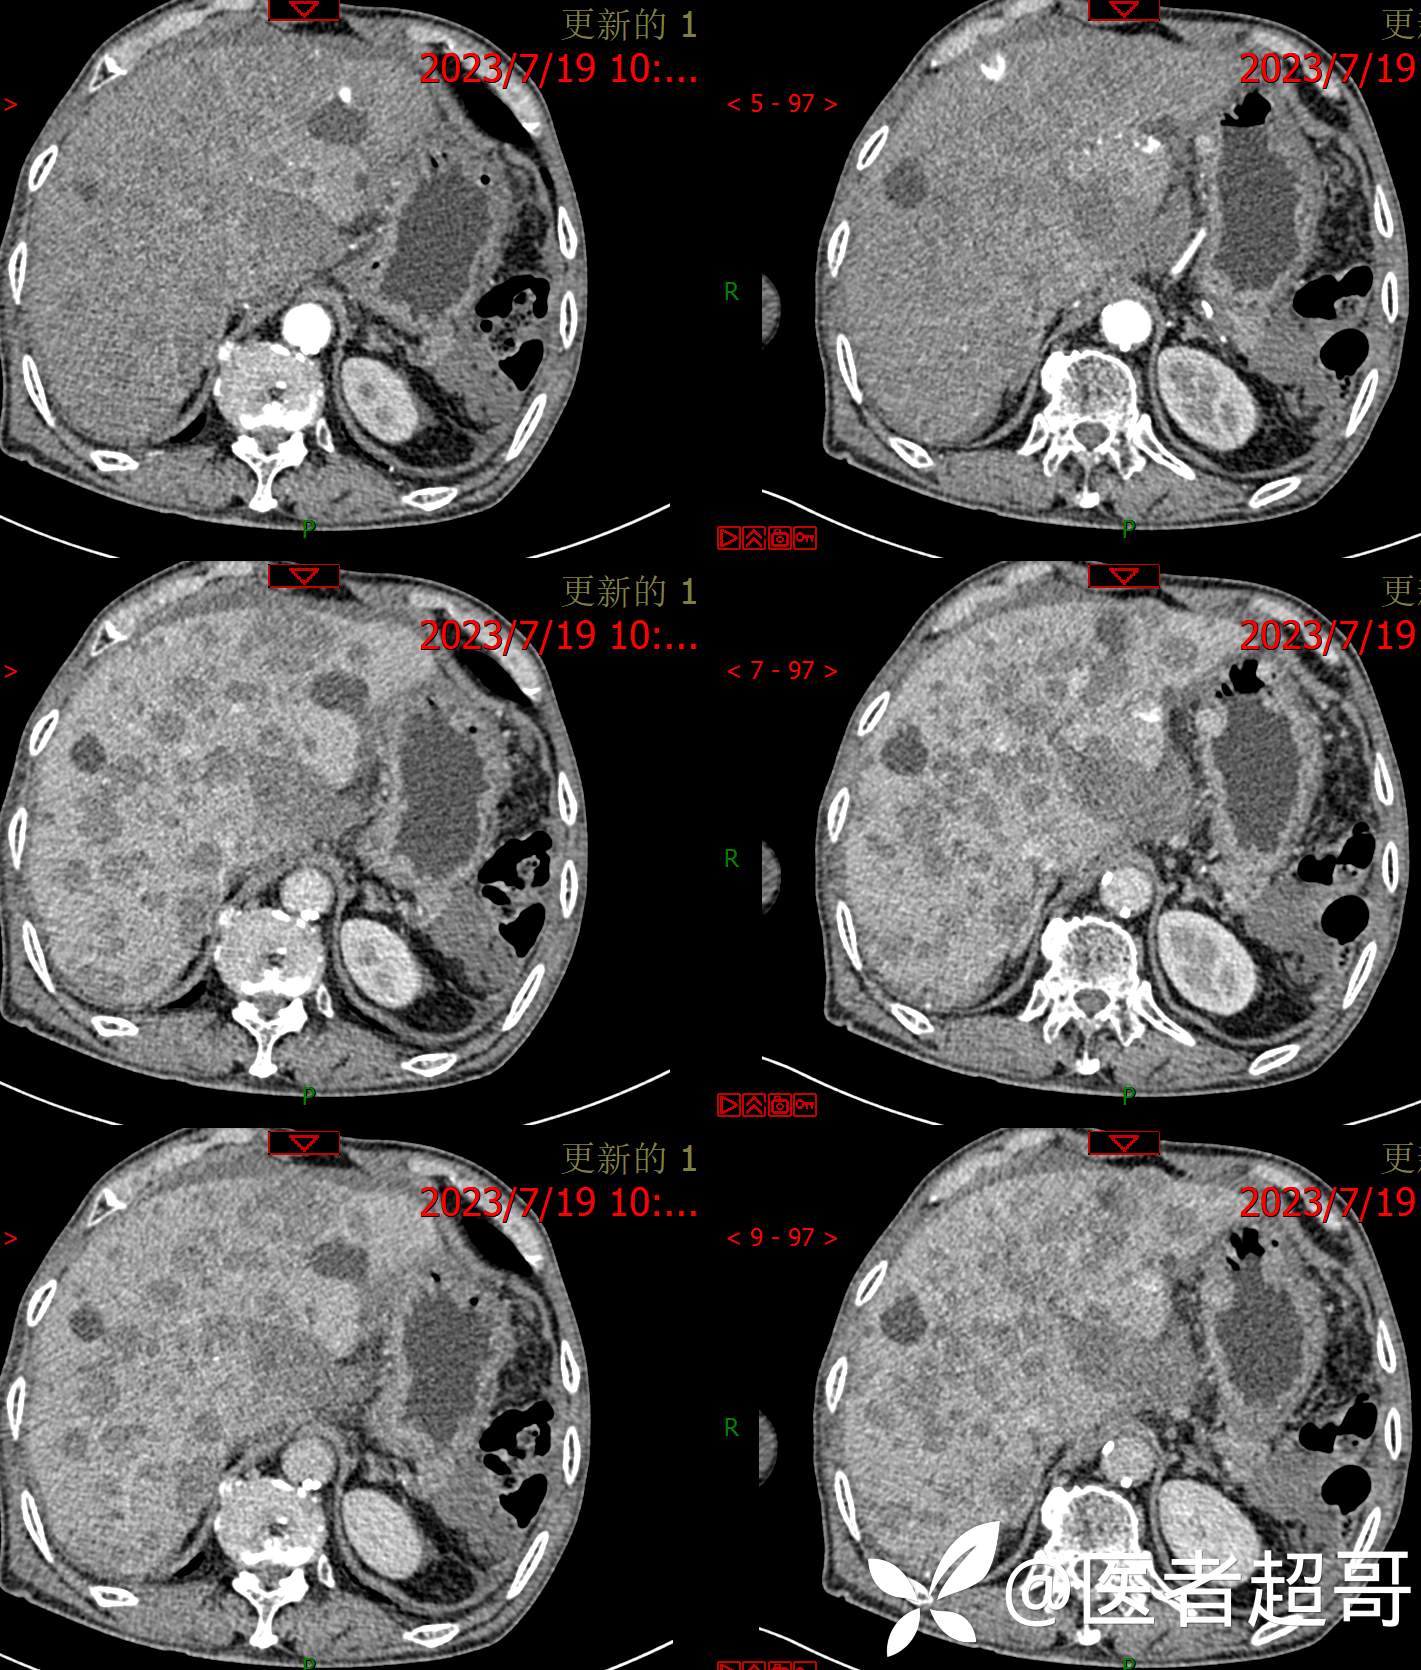

术后三个月复查CT、MRI表现: